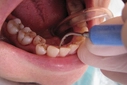

Diş Ekimi SüreciDiş ekimi süreci, genellikle birkaç aşamadan oluşur: